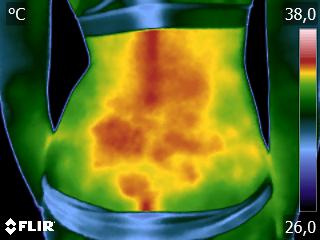

Como no caso da sequência de termogramas abaixo de uma paciente do sexo feminino, 51 anos e sem comorbidades e que sofreu um trauma de pé esquerdo durante a prática esportiva. Fez exame de Raio-X e não foi detectado fraturas, mas ainda apresentava muita dor. No 4º dia de pós trauma realizou uma Análise Termofuncional e foi detectado alterações térmicas condizente com processo inflamatório.

A terapia então foi ajustada para tratar esta lesão, não sobrecarregando a mesma e não apenas tratando a sintomatologia, mas sim até sua completa restauração.

Como no caso apresentado acima, a Termofuncional lhe proporciona não só “enxergar” as alterações térmicas, mas também uma maior segurança na terapia, com isso você poderá ter resultados muito mais eficazes. Além de lhe garantir segurança jurídica para cada procedimento que você realizar na sua reabilitação.